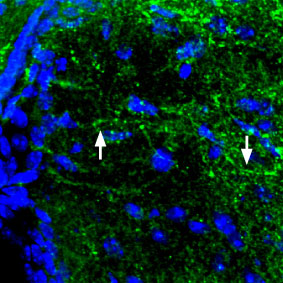

Expression of MC4R in mouse brain Immunohistochemical staining of perfusion-fixed frozen mouse brain sections using Anti-Melanocortin Receptor 4 (extracellular) antibody ( APR08420G), (1:100). MC4R (green fluorescence) is expressed in the mouse hypothalamus in axonal processes (arrows). Hoechst 33342 is used as the counterstain (blue). |